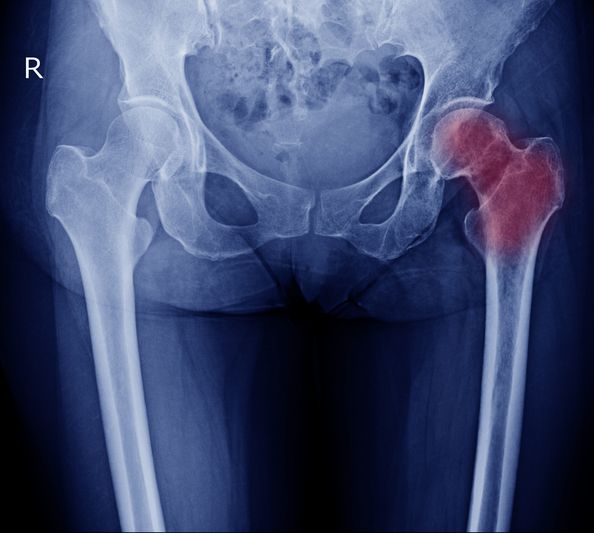

Вколоченный перелом шейки бедра без смещения

Перелом шейки бедра — это довольно тяжелая травма. После нее всегда возникают неприятные осложнения. Для людей преклонного возраста такая травма особенно опасна. Существует мнение, что если произошло повреждение, то это станет сразу очевидным. Суждение не всегда верно, поскольку перелом шейки бедра может быть вколоченным. В этом случае потерпевший сохраняет способность к передвижению в течение следующих нескольких дней. Сигналом того, что произошло повреждение, будет боль в области бедра. Устранить травму и облегчить состояние пациента может только профильный врач.

Вколоченный перелом шейки бедра у пожилых людей

Молодые люди сталкиваются с этим видом повреждений крайне редко. У них такой перелом возникает чаще всего в результате серьезных производственных, спортивных травм или после перенесенных автомобильных происшествий. По статистике, 90 % пациентов с этим повреждением — люди преклонного возраста. Обусловлено это тем, что лица старше 60 лет часто страдают от недостатка кальция в организме. В результате этого развивается остеопороз. Заболевание приводит к хрупкости костей. Малейшее воздействие на них может спровоцировать перелом. Для многих пожилых людей такой вид травмы считается очень опасным, поскольку если его тактика лечения подобрана неверно или помощь оказана не своевременно, то последствия повреждения могут привести к инвалидности, а в некоторых случаях даже к смерти.

При вколоченном переломе шейки бедра происходит смятие костей, и они вклиниваются друг в друга. Эта особенность и дала название травме. При таком переломе человек может передвигаться некоторое время, однако испытывает при этом сильную боль. К прочим симптомам повреждения относятся:

• характерный звук в процессе деформации;

• боль в области травмы, иногда она может отдавать в пах;

• трудности при передвижении;

• поврежденная конечность значительно короче, чем здоровая;

• невозможность приподнять больную ногу.

Пациент со вколоченным переломом, когда переворачивается на кровати, слышит характерный хруст в тазобедренном сочленении. Если ему постучать легонько по пятке больной конечности, то боль усиливается и иррадиирует в пах. При осмотре потерпевшего в положении лежа ступня поврежденной ноги находится в наружной ротации. Самостоятельно вправить стопу не представляется возможным.

К сожалению, такие симптомы могут долгое время игнорироваться человеком. Он продолжает перемещаться, и не обращается за помощью к врачу. В результате такого поведения, вколоченный перелом нередко трансформируется в обычный. Он уже требует гораздо более серьезного лечения и длительного реабилитационного периода.

Вколоченный перелом шейки бедра без смещения — считается одной из более благоприятных форм. Проявляется болью в тазобедренной области и ограничением движений. Без терапии возможны осложнения и переход в открытый перелом. Также усиливается риск нарушения кровоснабжения головки бедренной кости. Это состояние требует ограничения нагрузки и длительной иммобилизации. Без терапии возможны остеонекроз и хроническая боль.